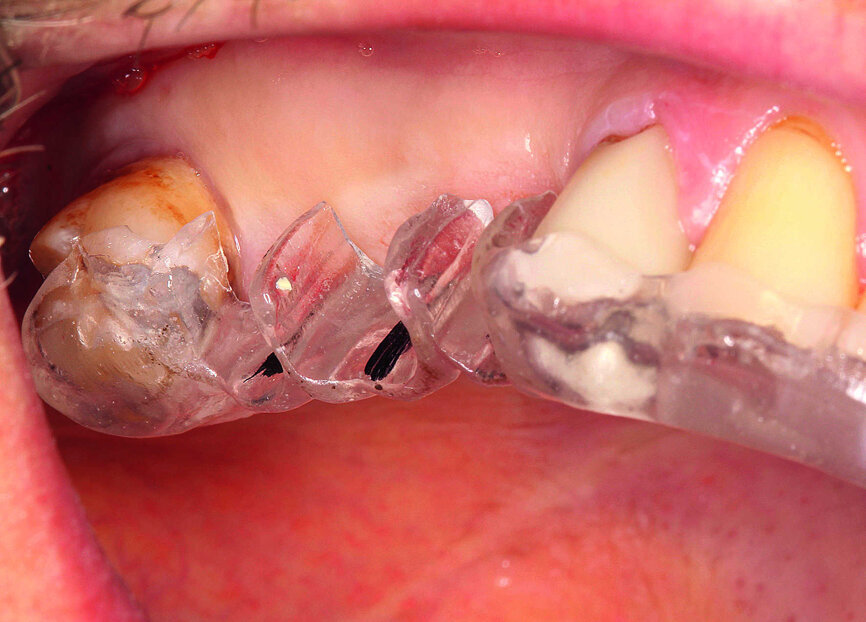

Fig. 19 : Vue latérale des coiffes d’empreinte.

Les implants et la morphologie de la mâchoire ont été moulés pour la fabrication des piliers individualisés en zircone. La prise d’empreintes en technique à ciel ouvert a requis le dévissage des façonneurs gingivaux, de façon à permettre la mise en place de coiffes d’empreinte en PEEK. Une certaine expérience est nécessaire pour vérifier la précision de l’ajustement sur la radiographie de contrôle, car seule la périphérie du matériau est radio-opaque (Figs. 19 et 20).